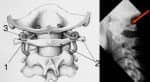

La segunda causa más común de dolores de cabeza son las enfermedades de la columna cervical (osteocondrosis) o el sobreesfuerzo de los músculos del cuello (cuando la cabeza está en la posición incorrecta durante el trabajo o el sueño).

Si el dolor se concentra en la región occipital, lo más probable es que el problema esté en una de las secciones de la columna, que desborda la arteria, interfiriendo con el drenaje normal de la sangre. Síntomas similares son causados por cambios ateroscleróticos en el sistema cardiovascular, que provocan un aumento de la presión arterial.